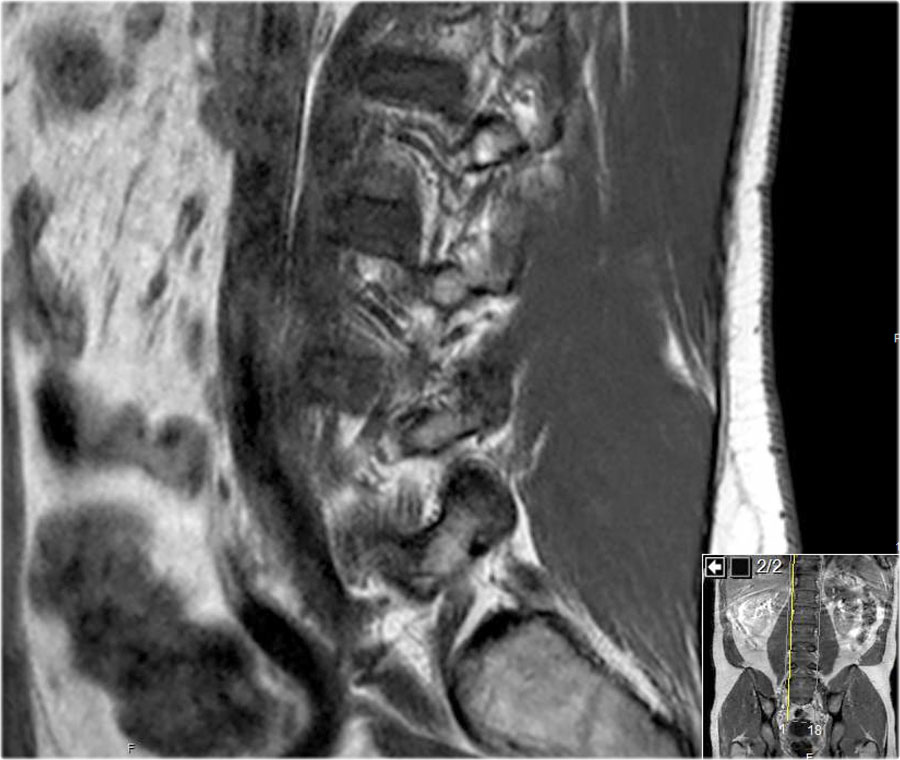

Cuộn qua các hình ảnh để quan sát đường đi của các rễ thần kinh tại mức độ đĩa đệm, ngách bên, lỗ liên hợp và ngoài lỗ liên hợp.

Tại mỗi mức độ có thể thấy các bệnh lý đặc trưng, nhưng có sự chồng lấp đáng kể.

Ví dụ, đĩa đệm có thể thoát vị và gây chèn ép thần kinh tại mức độ đĩa đệm, nhưng cũng có thể di trú xuống tầng thấp hơn và chèn ép rễ thần kinh trong ngách bên, hoặc di chuyển lên trên và gây chèn ép tại mức độ lỗ liên hợp hay ngoài lỗ liên hợp.

Ở bệnh nhân thoái hóa khớp mỏm khớp, các gai xương có thể phát triển vào trong và làm hẹp ngách bên, hoặc phát triển lên trên và làm hẹp lỗ liên hợp.

Khi thoái hóa khớp mỏm khớp nặng xảy ra hai bên, có thể gây hẹp ống sống và chèn ép tất cả các rễ thần kinh tại tầng đó.